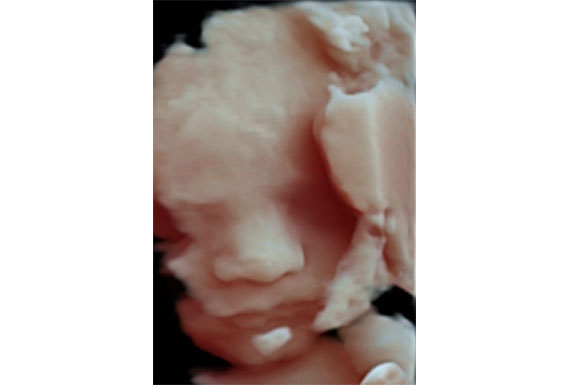

Centrus, brinda Ultrasonido Médico Diagnóstico, con profesionales dedicados, y con un alto grado de experiencia.